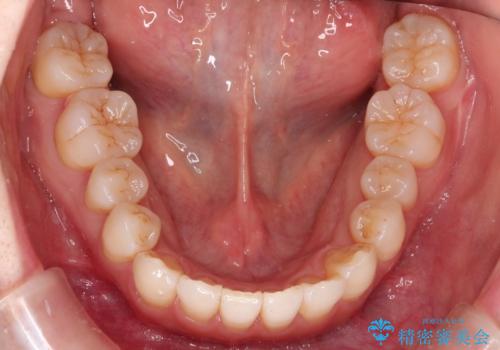

インビザラインで八重歯の矯正

- 八重歯を治したいとのことで、来院されました。

インビザラインにて、上顎の歯と歯の間をわずかに削り、並べる計画としました。

使用時間を守っていただけたので、比較的スムーズに矯正を終了することができました。